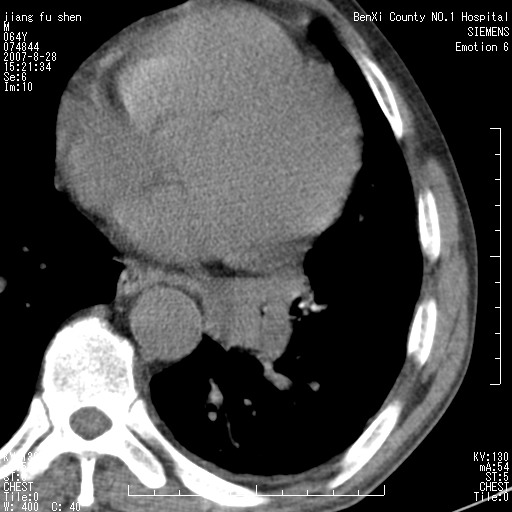

男、64、咳嗽、发烧一周、左肺呼吸音稍弱。既往肺结核,右手结核。

本次扫描患者未带原片,左肺下叶发现病灶。左肺上叶空洞,5组淋巴结肿大,1cm左右。

平扫20-33hu

增强31-33hu

1分半44-52

2分55-67

左肺下叶前内基底段支气管明显偏心性狭窄,周围分叶状肿块,伴有阻塞性肺炎,支持肺癌可能性大。

考虑左肺中央型肺癌并阻塞性肺炎

病灶边缘可见多量较长棘影及纤维条索状影,除外病灶边缘较光整,病灶有分叶表现,但多表现为较浅分叶,且向周围伸出之叶多呈尖角改变,且边缘较光整,病灶增强呈中度延时增强,且早期及中期仅轻度增强,结合患者病史,多考虑继发型肺结核,炎性增殖灶形成,不除外肺癌